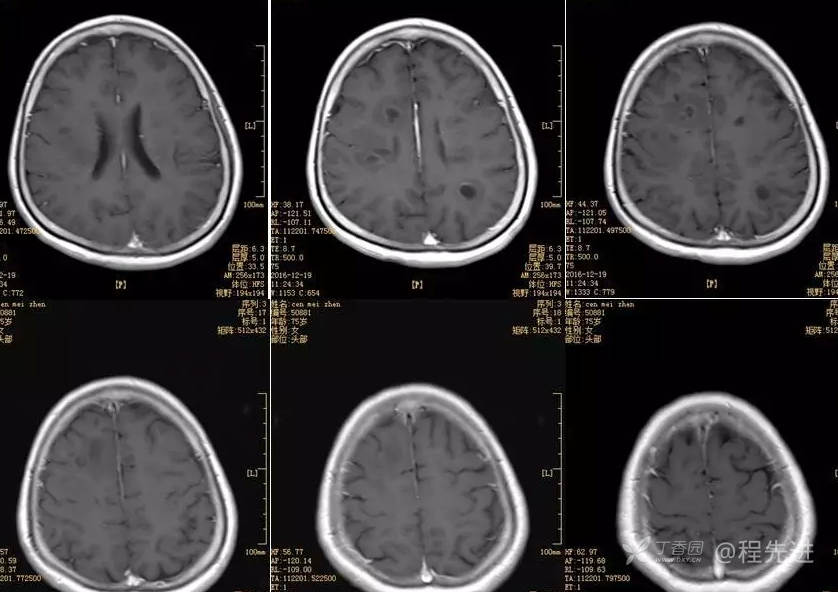

辅助检查:

胸片未见异常。

腰穿压力150cmH20

脑脊液常规

颜色 无色

凝固性 阴性

透明度 清晰

潘氏球蛋白定性试验 +-

LDH 27U/L

葡萄糖 5.10mmol/L高

蛋白 368.4mg/L

氯化物 127.2mmol/L

红细胞总数 1000*10^6/L高

白细胞 6*10^6/L

中性(多核) 33.3%

淋巴(单核) 66.7

间皮 0

涂片未见细菌、结核菌、新型隐球菌